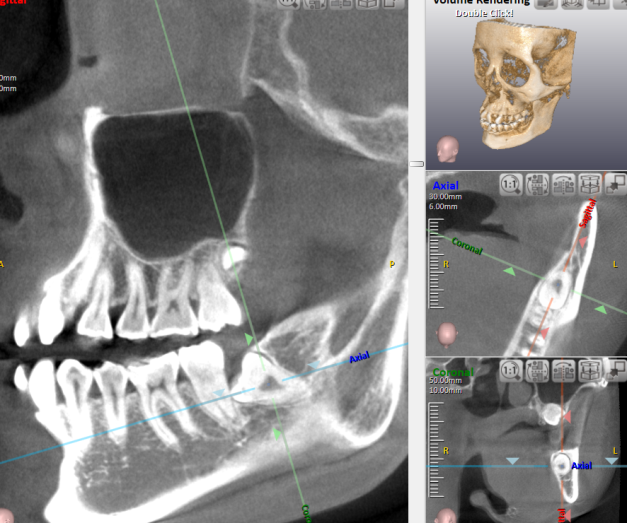

問診とレントゲン撮影:全身疾患やアレルギー、常用している薬などの確認を行います。また、レントゲン撮影を行い、親知らずの位置や角度、周囲の神経や血管の位置を確認します。

◆横向きに生えている親知らず:歯を砕きながら抜歯する必要があります。抜歯時間は約30分です。

◆骨の中に潜っている親知らず:被っている歯茎や骨を取り除き、親知らずを砕いて抜歯する必要があります。抜歯時間は約5分です。